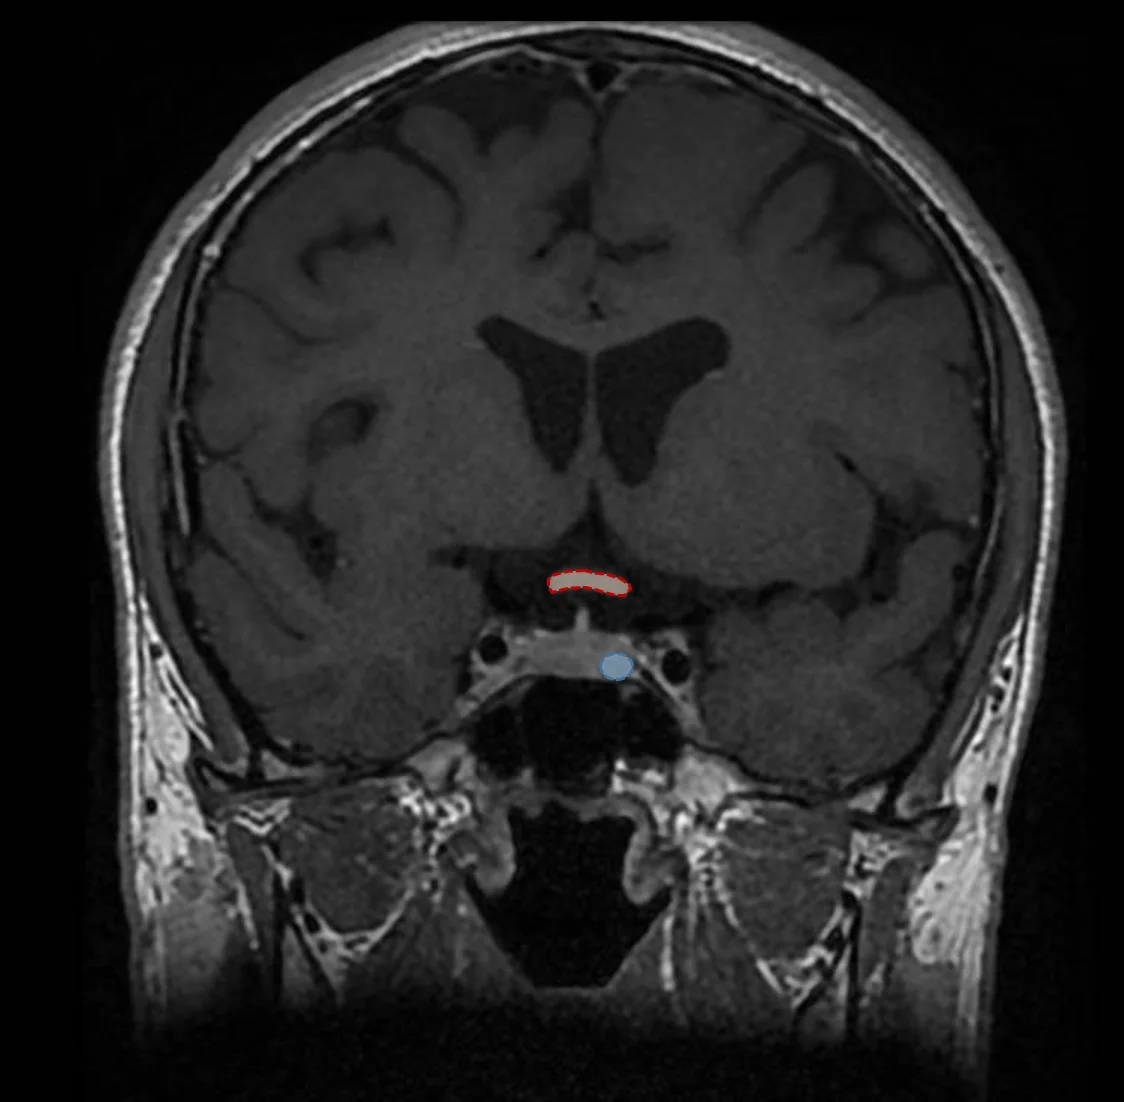

Le diagnostic d’adénome hypophysaire repose sur deux éléments que sont l’imagerie médicale et le bilan endocrinien. L’examen de référence à réaliser dans la recherche d’un adénome est une IRM cérébrale, qui permettra d’en évaluer la taille et le retentissement sur les structures adjacentes, notamment les voies visuelles. Les adénomes sont habituellement classés en deux groupes: les micro-adénomes (de moins de 10 mm de diamètre) et les macro-adénomes (de plus de 10 mm de diamètre). Le bilan endocrinien va quant à lui permettre de déterminer le niveau de sécrétion des différentes hormones sécrétées par l’hypophyse ainsi que leur retentissement sur l’organisme.

De par leur position à la base du cerveau, au sein de la selle turcique, une structure osseuse contenant l’hypophyse, les adénomes hypophysaires peuvent dans un grande majorité des cas être opérés sans ouvrir la boîte crânienne en passant par l’intérieur des fosses nasales. La chirurgie est habituellement courte (30 à 60 minutes), sans cicatrice visible, avec une hospitalisation en moyenne de 3 jours.